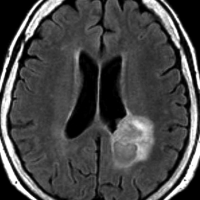

高齢者の無症候例です

60代の女性に無症候で発見された稀な部位のPXA。結節様ですが脳とのはっきりした境はなく,多房性ののう胞を伴っていました。T2とFLAIR像ではわずかな浸潤像あるいは腫瘍周辺浮腫が疑われます。PXAに特徴的な画像ですが,大脳深部発生でもあり,PXAと画像診断することはできません。定位脳生検術 MRI-guided sterotactic biopsyで病理組織診断を行ない経過観察しました。

3年観察したら嚢胞を伴って増大しました。幸いのう胞性拡大が脳表方向であったのでparietal transcortical approachで全摘出できました。側脳室三角部腫瘍への到達法と同じアプローチですが,この経路では頭頂葉症候を後遺することがありません。

術後は無症状で8年間再発はありません。